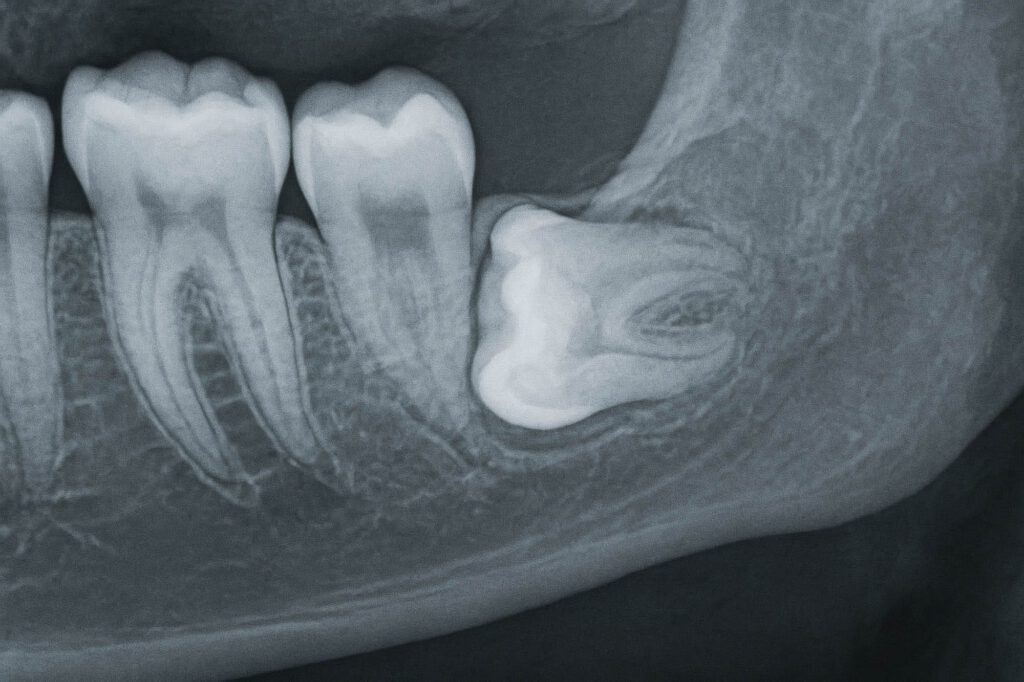

Ob eine Entfernung notwendig ist, entscheiden unsere Zahnärzte im ZAHNZENTRUM LIPPE anhand von detaillierten Röntgenaufnahmen. Diese zeigen die Lage und Wachstumsrichtung der Weisheitszähne und erlauben eine individuelle Behandlungsplanung. Eine frühzeitige operative Entfernung – oft bereits vor dem vollständigen Durchbruch – kann spätere Komplikationen verhindern.